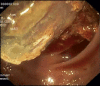

Colonic Intussusception Caused by Colonic Lipoma